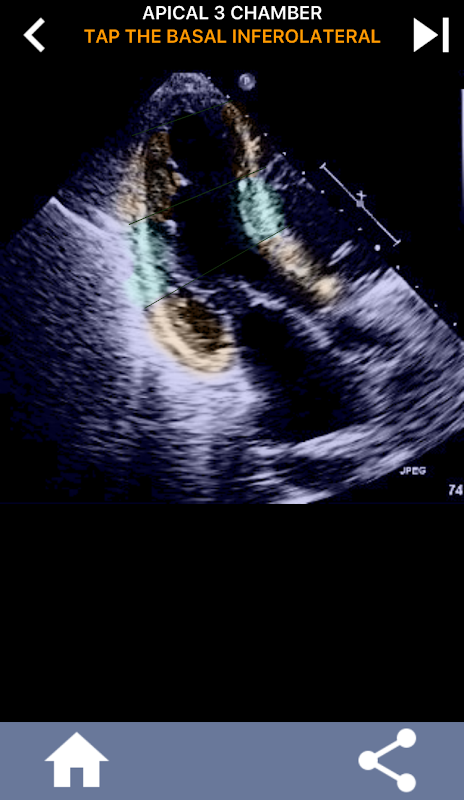

Diese App enthält alle Echoansichten, die das AHA-segmentierte Myokard anzeigen, und fragt Sie, ob Sie das richtige Segment antippen möchten. Ich persönlich finde, dass sich wiederholendes Quiz am besten für mich eignet, wenn ich das Thema schnell lernen / auswendig lernen muss. Wenn Sie ein Ultraschall-Student sind, der Echo / TTE studiert, ist dies meiner Meinung nach eine hervorragende Ergänzung zu Ihrem Studium.